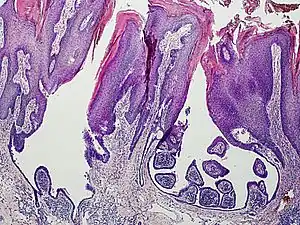

Syringocystadenoma papilliferum

Syringocystadenoma papilliferum is a benign apocrine tumor.[1]